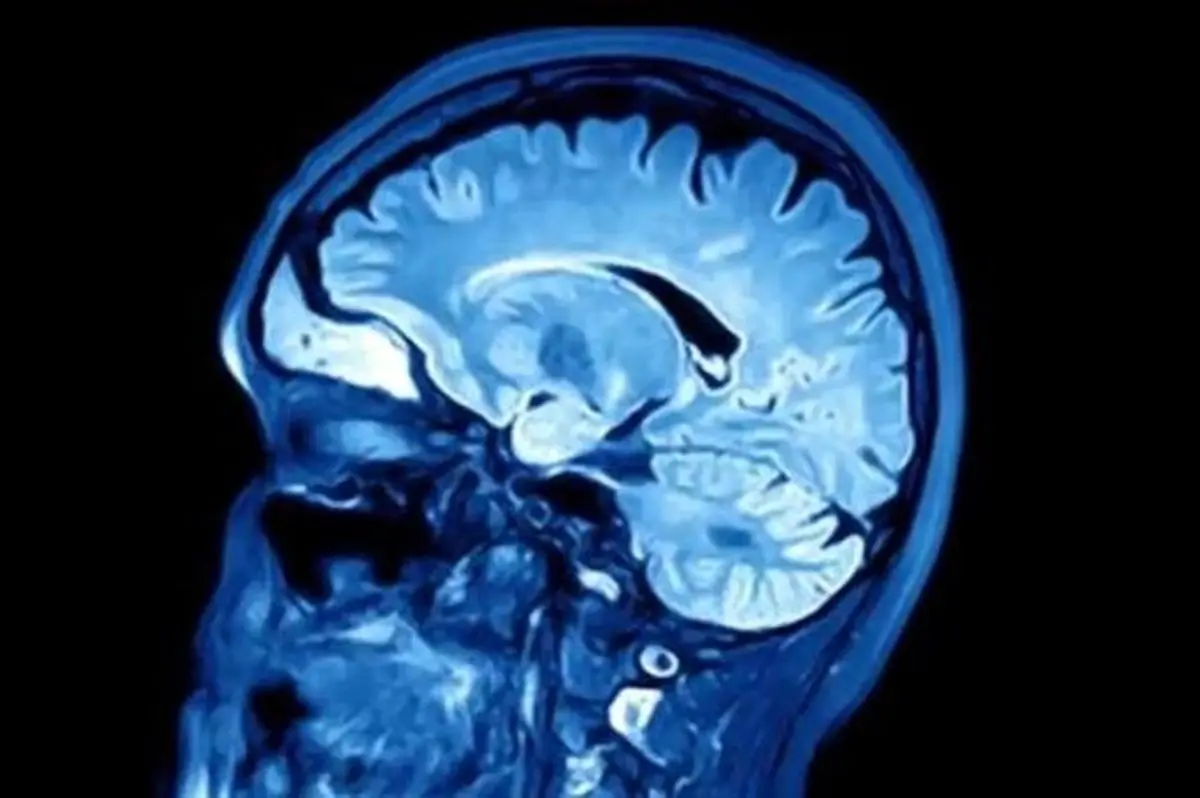

محققان دریافتند افرادی که هنگام بلند شدن، احساس سرگیجه می‌کنند بیش از سایرین در معرض ابتلا به زوال عقل قرار دارند.

محققان دریافتند تنها آن دسته از افراد که در هنگام ایستادن دچار افت فشار سیستولیک می‌شوند، در معرض ابتلا به زوال عقل هستند و افت فشار دیاستولیک یا فشار خون به طور کلی، ارتباطی با این بیماری ندارد.

فشار سیستولیک، اولین عددی است که در هنگام گرفتن فشار خون خوانده می‌شود و به اعتقاد محققان افت این فشار به میزان ۱۵ واحد در هنگام ایستادن، نشان‌دهنده خطر ابتلا به زوال عقل است و کنترل این افت فشار می‌تواند راهکار مناسبی برای حفظ حافظه و مهارت‌های شناختی افراد در سنین بالا شود.

این تحقیقات با کمک دو هزار و ۱۳۱ داوطلب سالم با میانگین سنی ۷۳ سال انجام شد. فشار خون این افراد یک بار در ابتدای مطالعه و سپس در فاصله یک سال، ‌ سه سال و پنج سال بعد باردیگر اندازه‌گیری شد. در این مدت در مجموع ۱۵ درصد از داوطلبان دچار افت فشار خون شدند که در ۹ درصد آنها افت فشار سیستولیک و در ۶ درصد دیگر دیاستولیک بود. در طول ۱۲ سال بعد، داوطلبان همچنان تحت نظر قرار گرفتند تا در صورت ابتلا به زوال عقل، شناسایی شوند. در این مدت مجموعا ۴۶۲ نفر از داوطلبان یعنی ۲۲ درصد از آن‌ها دچار زوال عقل شدند.

با بررسی این افراد مشخص شد احتمال ابتلای افراد دارای افت فشار سیستولیک به زوال عقل نزدیک به ۴۰ درصد بیش از سایرین است.

آلزایمر شایع‌ترین نوع زوال عقل است. یکی از مهم ترین دلایل بروز آلزایمر، تجمع پلاک‌های پروتئین آمیلوئید در مغز است. آمیلویید یک اصطلاح عمومی برای پروتئین‌هایی است که به طور طبیعی در بدن بوجود می‌آیند. در مغز افراد سالم، این پروتئین نابود می‌شود ولی در مغز افراد مبتلا به آلزایمر، تجمع می‌یابد.

در حال حاضر حدود ۵۰ میلیون نفر در جهان به زوال عقل مبتلا هستند و سالانه حدود ۱۰ میلیون نفر به این تعداد افزوده می‌شود. گزارش کامل این تحقیقات در نشریه Neurology منتشر شده است.